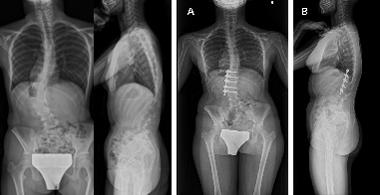

重度脊柱変形に対する矯正固定術

さまざまなお体の病気に伴いせぼねが重度に変形を起こし、息切れなどの症状が出る場合があります。これらの患者様に対しては状況に応じて、せぼねを矯正固定する場合があります。小児科やリハビリテーション科と相談しながら手術時間や入院期間を検討していきます。

-

脊髄性筋萎縮症の重度後側弯症に対する後方矯正固定術

グローイングロッド手術

せぼねの変形が進行して矯正固定術を要すると考えられるが、体がまだ小さなこどものお子様にはせぼねを固定せずに6ヶ月に1度の30分程度の小さな手術を繰り返すことで、せぼねを成長させる手術を選択する場合があります。概ね10歳以下で手術が必要な患者様が対象となります。

点状軟骨異形成症に伴う後側弯症に対するグローインロッド手術